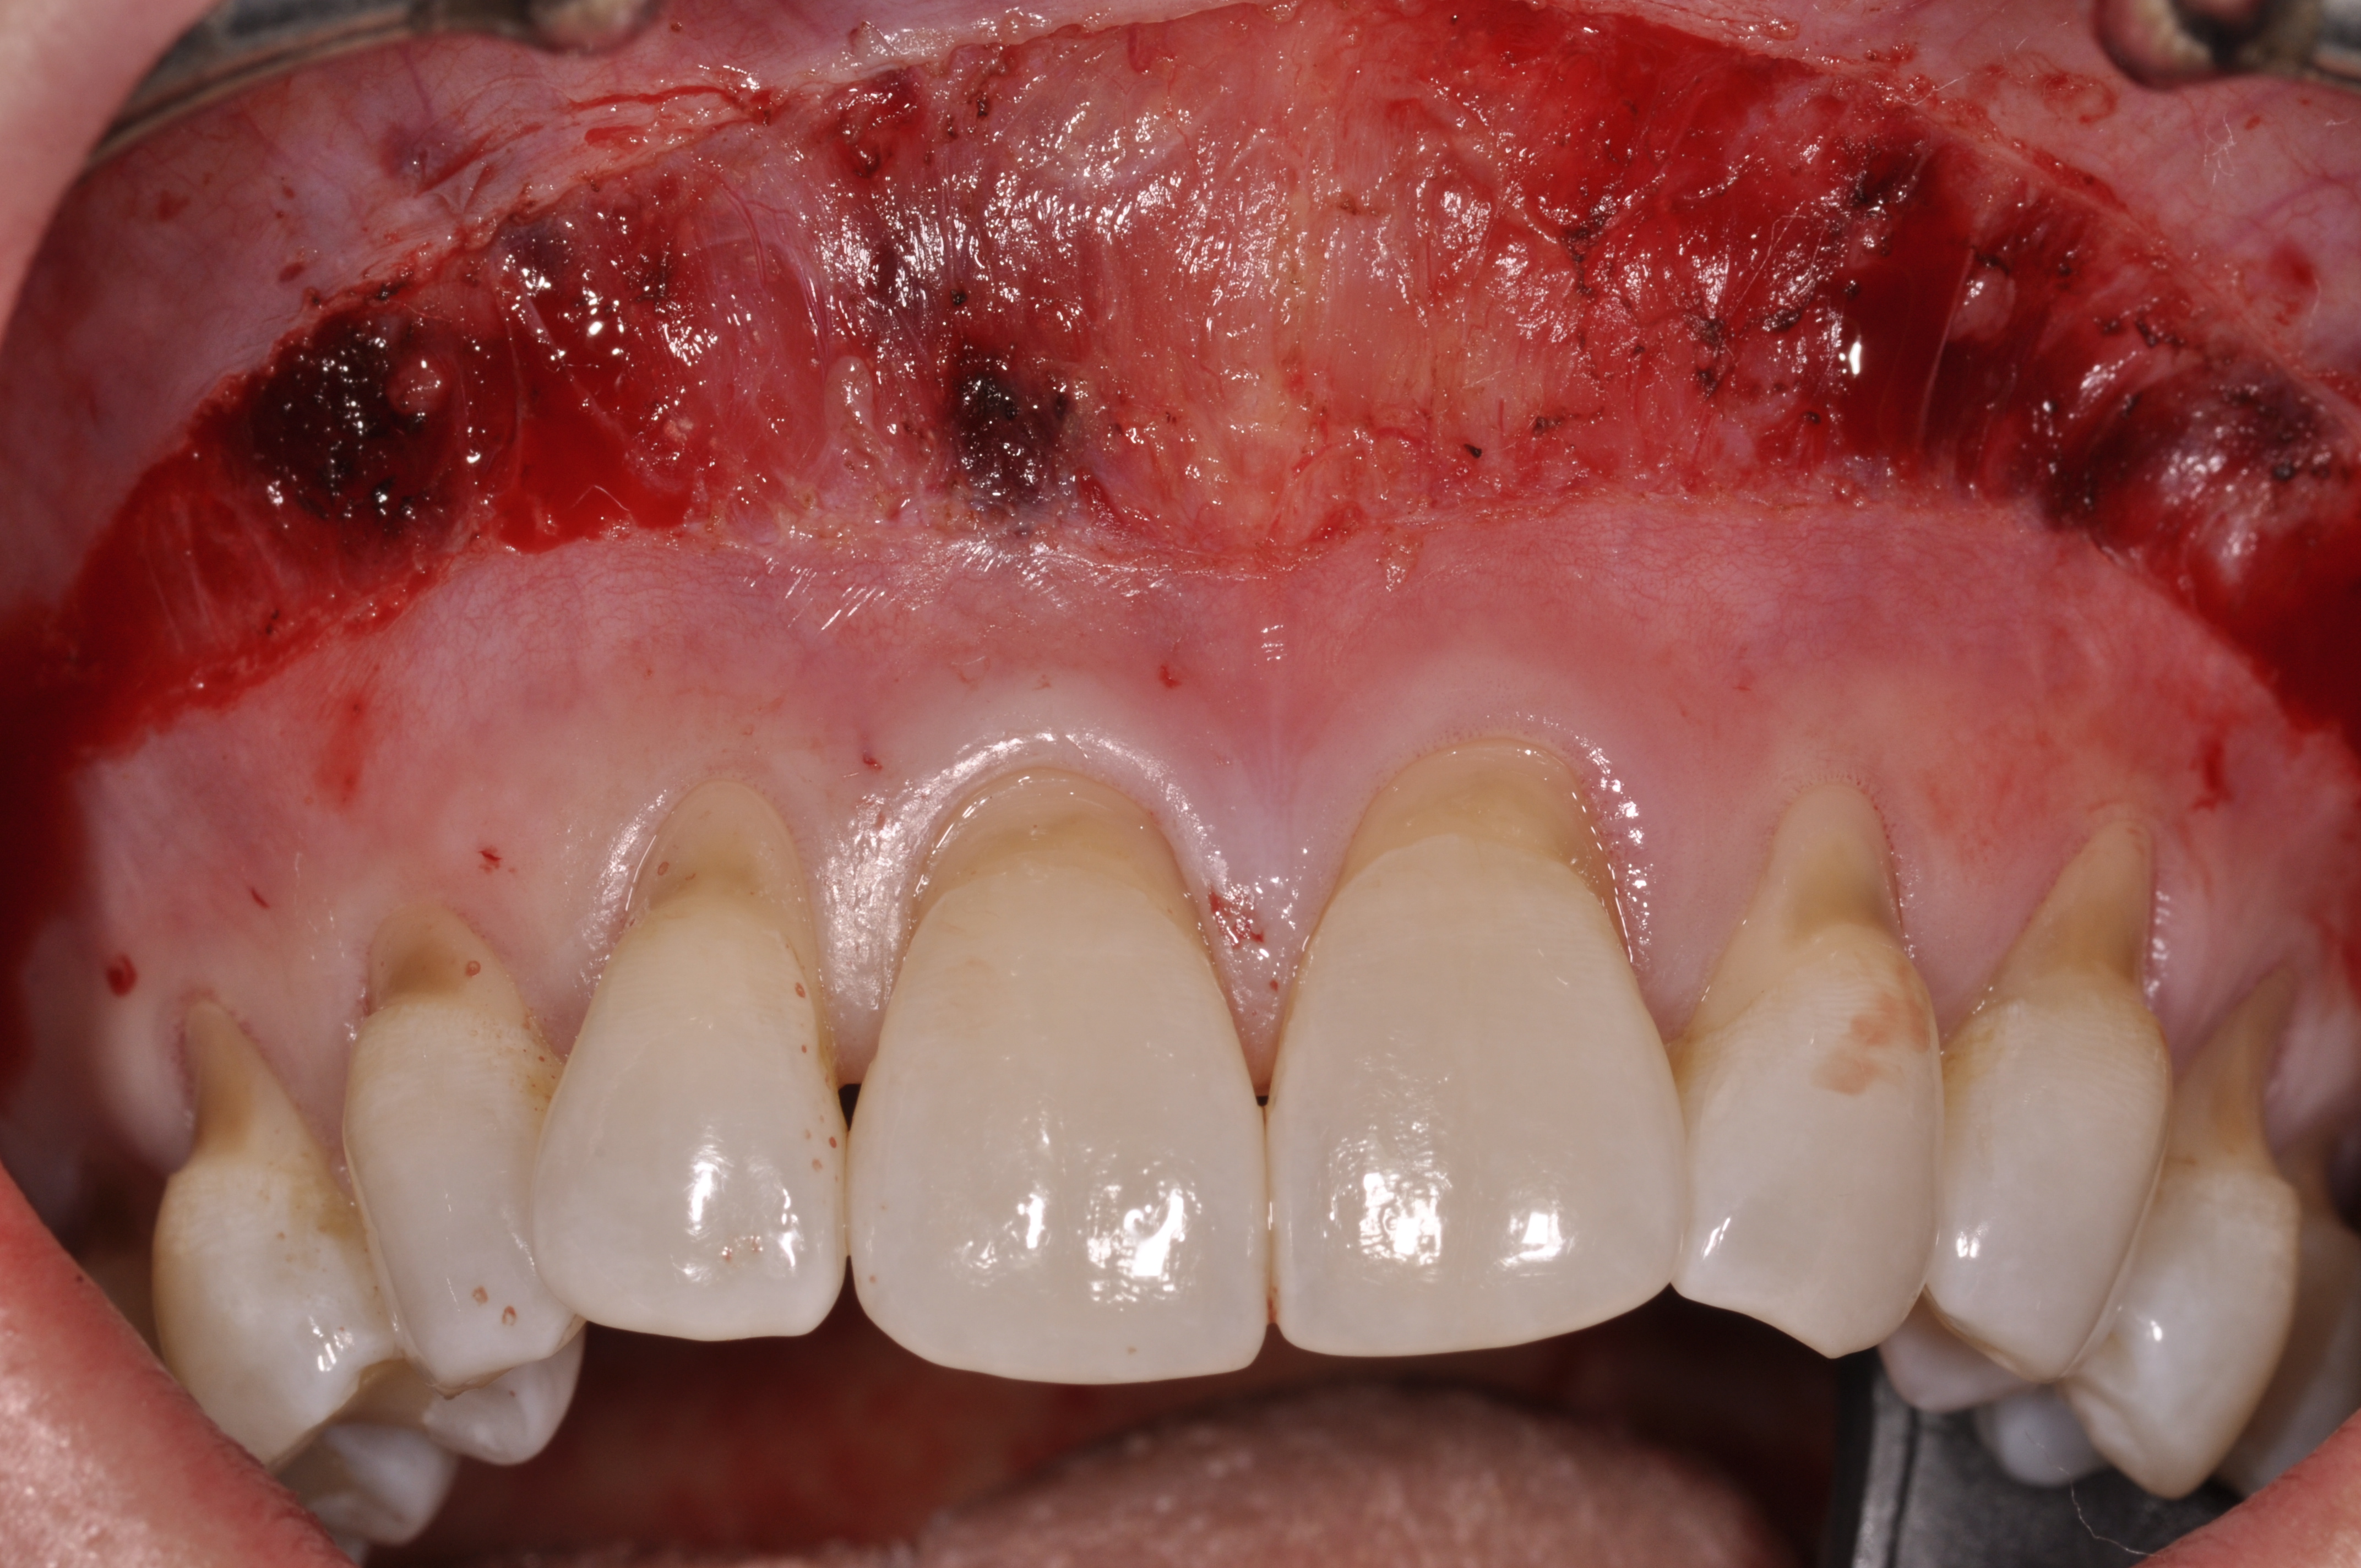

Fig 1. Preoperative clinical view, mandibular central incisor.

Figure 1

Fig 6. Pretreatment clinical view, maxillary left anterior sextant, of case presented.

Figure 6

Case Report

A 24-year-old, nonsmoking man presented for correction of gingival clefting and recession in the maxillary left anterior sextant (Figure 6). The patient’s medical history was noncontributory. After consultation and presenting various options to the patient to correct the localized recession, the patient opted for the use of acellular dermal matrix tissue rather than harvesting tissue from his palatal area.